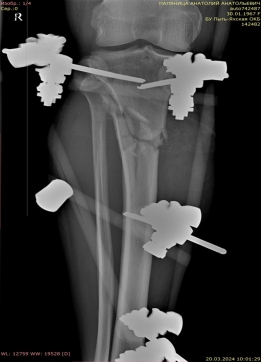

2) Мужчина, 57 лет. В результате падения бревна на область голени получил травму — открытый оскольчатый перелом верхней трети диафиза правой большеберцовой кости со смещением отломков (рис. 4).

Рис. 4.